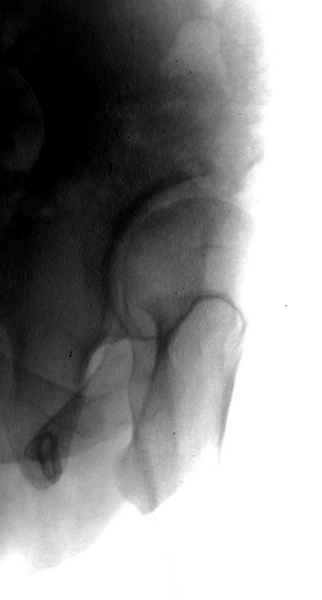

А для данного случая, необходим прямой снимок таза с отдельными суставами, также включить боковые снимки сустава, немаловажно знание покрытия головки спереди.

Большое спасибо коллегам, которые укрепили меня в моих сомнениях.А сомнения родились после того, когда больной, направленный мною для эндопротезирования, вернулся после операции экскохлеации кистозных полостей и костной аутопластики из гребня.Диагноз клиники -фиброзная дисплазия,со слов пациента подтвержден гистологически.Через несколько месяцев он бросит костыли и скорее всего вновь появятся боли и симптом Тренделенбурга.В подобных случаях с 86 года у нас производились варизующие остеотомии и многие больные избежали ТЭП.причем оперировали вначале манифестный сустав, убеждали и через год корригировали второй.Перед операцией делаем снимок в прямой проекции с максимальным приведением-отведением, оценивая позиционирование головки.Попытаемся убедить больного через 6-7 мес. в необходимости операции коррекции ШДУ.